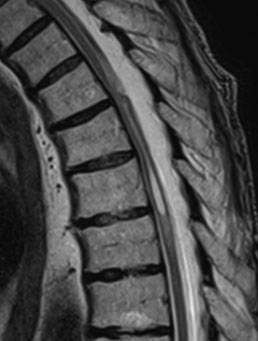

Головний метод діагностики – МРТ, на якому виявляється зміщення спинного мозку та зона притискання спайкою у вигляді «скальпеля». А також, виявляється зона мієлопатії (зона набряку спинного мозку).

Контроль МРТ після операції – добрий. Зона мієлопатії – зменшилася та стала менш інтенсивною.